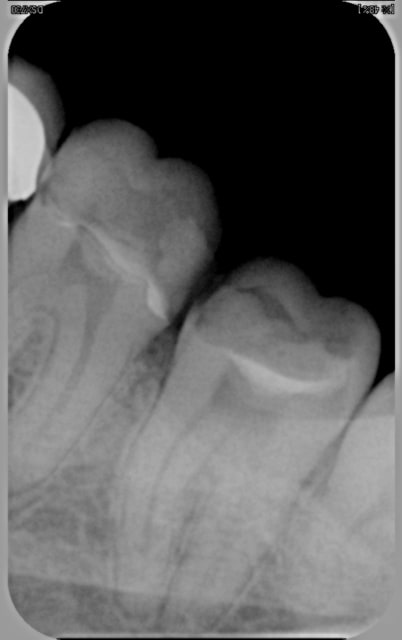

Retirer les excès devient vraiment très compliqué quand les dents sont serrées (pas de place pour passer une sonde même fine) et que la limite cervicale proximale est basse.

Pas exemple dans ce cas de figure sur la radio, préparations pour 2 inlays sur 36 et 37.

Le risque c'est de pousser la colle vers le sulcus au lieu de la retirer.